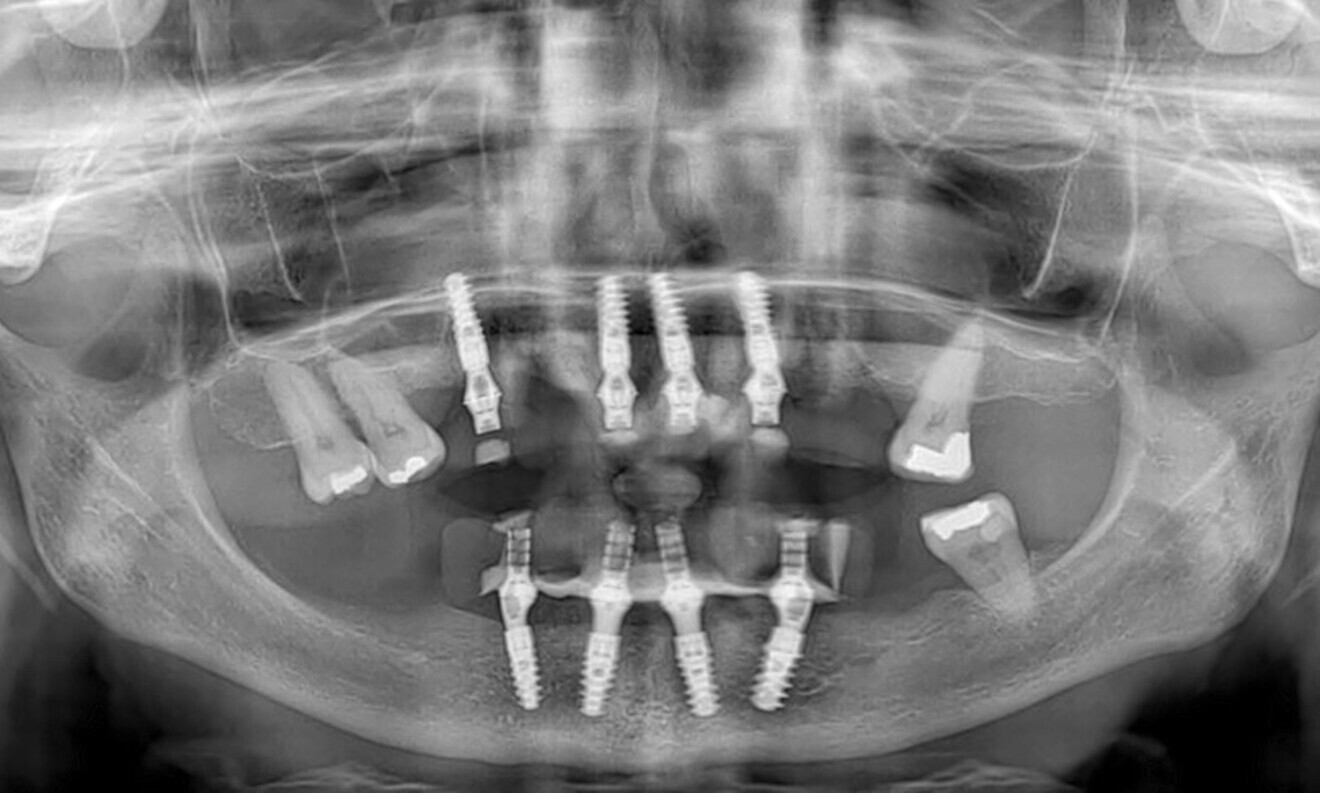

On the day that the sutures were removed, excellent healing was observed. The follow-up radiograph also confirmed the proper positioning of the implants (Figs. 67 & 68).

Fig. 67: At the suture removal appointment, excellent healing was observed, ...

Fig. 68: ... and the radiograph confirmed proper implant positioning.

A follow-up was performed six months after surgery. The radiographic examination conducted at that time confirmed the successful integration and stability of the implants (Fig. 84).

Fig. 84: The six-month post-op radiographic evaluation confirmed successful implant integration and stability.